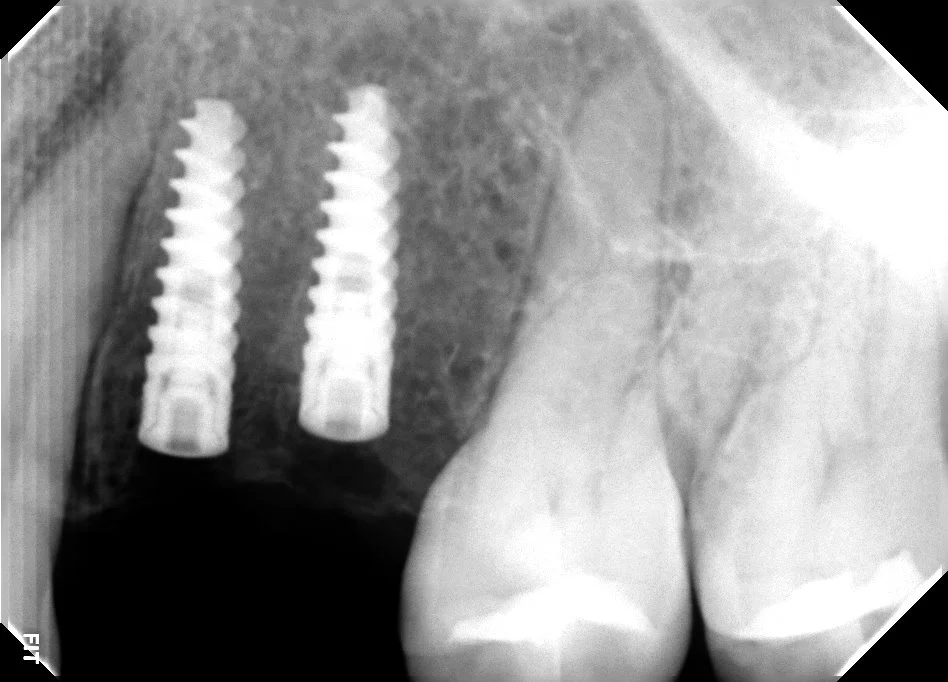

El sistema guiado para implantes ayuda a una colocación del implante de acuerdo a una planeación digital.

El proceso de colocación de implantes se realiza mediante un flujo digital, lo que nos asegura una planeación adecuada y segura para la adecuada colocación del implante dental.